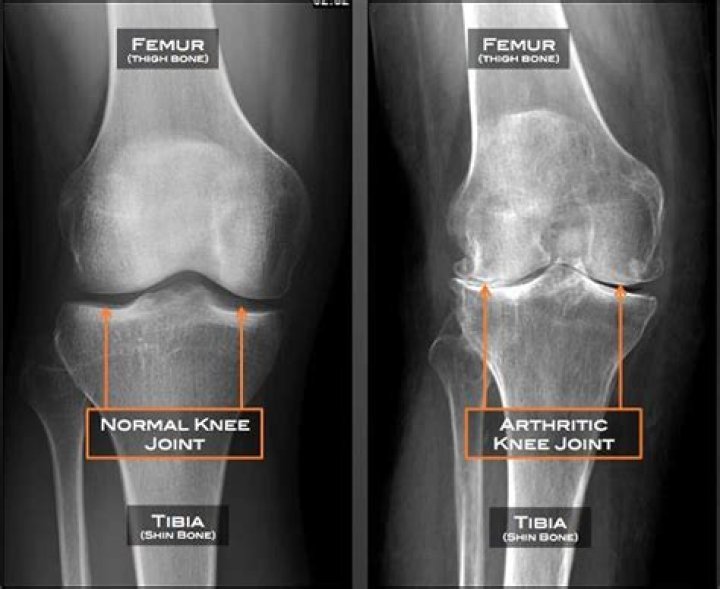

The main difference between osteoarthritis and rheumatoid arthritis is the cause behind the joint symptoms. Osteoarthritis is caused by mechanical wear and tear on joints. Rheumatoid arthritis is an autoimmune disease in which the body’s own immune system attacks the body’s joints. It may begin any time in life.

In severe, or advanced, OA: Your cartilage has worn away. The space between the bones in your joint is much smaller than it used to be. Your joint feels warm and is inflamed.

End-stage arthritis is the progressive wearing down of the cartilage that is present between the bones of a joint causing the bones to come in contact with each other and painfully rub against each other during movement of the joint. This results in severe pain with loss of movement and function.